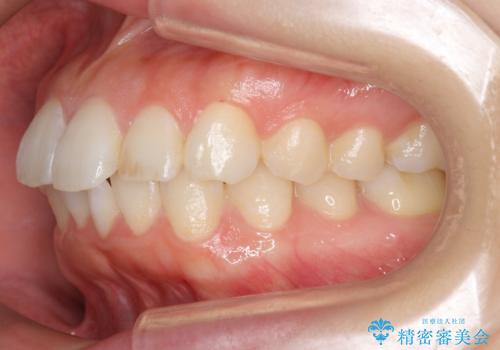

前歯のがたつき インビザラインで

治療症例の内容

- 前歯のがたつきを治したいとのことでした。歯を抜かずにできる範囲で引っ込めたいとのことでした。

歯列の側方拡大(横に広げる)と、エナメル質の削合で並べました。

歯を抜いているわけではないので、口元はそこまで変化はありませんが、前に出すことなくデコボコは取れたと思います。